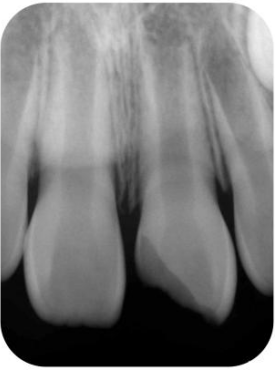

根管治疗的概述,难易风险的评估,牙髓病、根尖周病的诊断 规范化根管治疗的操作流程 X线根尖片的要求、拍摄技巧及信息的判读 开髓口的设计,冠方直线通路的建立,根管口查找的技巧

手动锉的探查与疏通 根管长度与根管预备长度的确定 根管预备的宽度确定 根管预备的逐步后退法 根管预备的冠向下法 弯曲根管的预备方法 根管化学预备的常用药物及浓度 化学预备的器械与药物使用步骤 实操:在透明模块和离体牙上实操镍钛锉根管预备